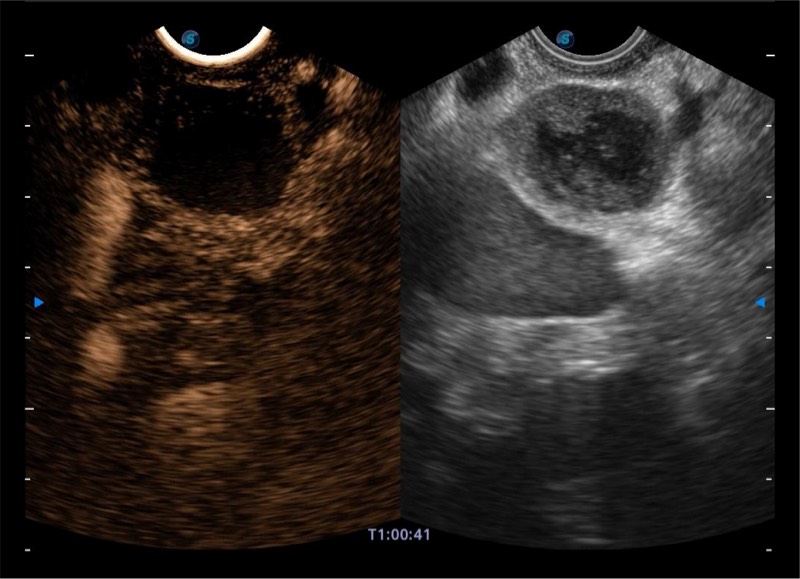

搭载百万级CMOS成像技术

及自主研发凸阵换能器,

可呈现优质的内镜和超声画面

基于二十年的超声技术积累,亚星官网提供了最新一代的独立超声主机,在提供高质量图像的同时满足多学科使用。具备常见多普勒技术并提供弹性成像、声学造影等高端影像技术。新一代传感器具有更强的抗干扰能力并减少图像伪影。